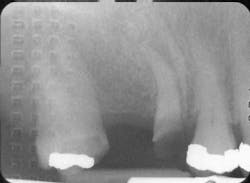

If the patient is at high risk —

Possible inadequate saliva flow, evident cavitation and radiographic lesions, and a high number on the bacterial test will require a multiple approach and a staged treatment plan.